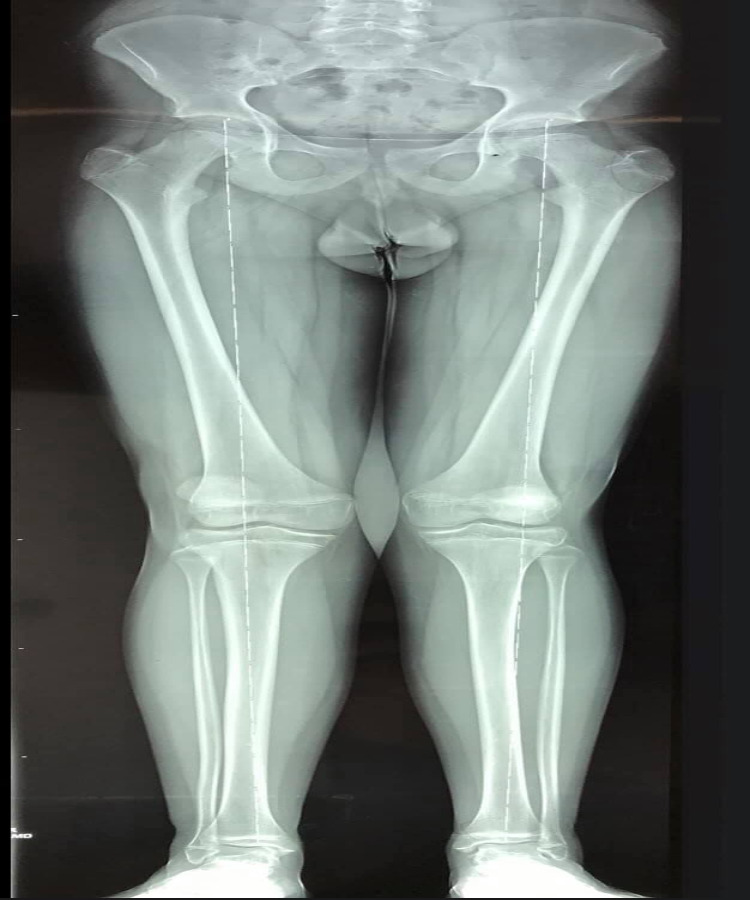

Rodillas en valgo con rótula alta

Él es mi pacientito Cristian, quien a sus 13 años me visitó para la revisión de sus rodillas porque le dolían al jugar fútbol. Le diagnosticamos rodillas en valgo con rótula alta. El tratamiento consistió en una cirugía de descenso rotuliano y crecimiento controlado de rodilla para corregir la deformidad. A los 6 meses del tratamiento, pudo correr y jugar fútbol sin problemas. Ahora tiene 15 años y ya lo di de alta.